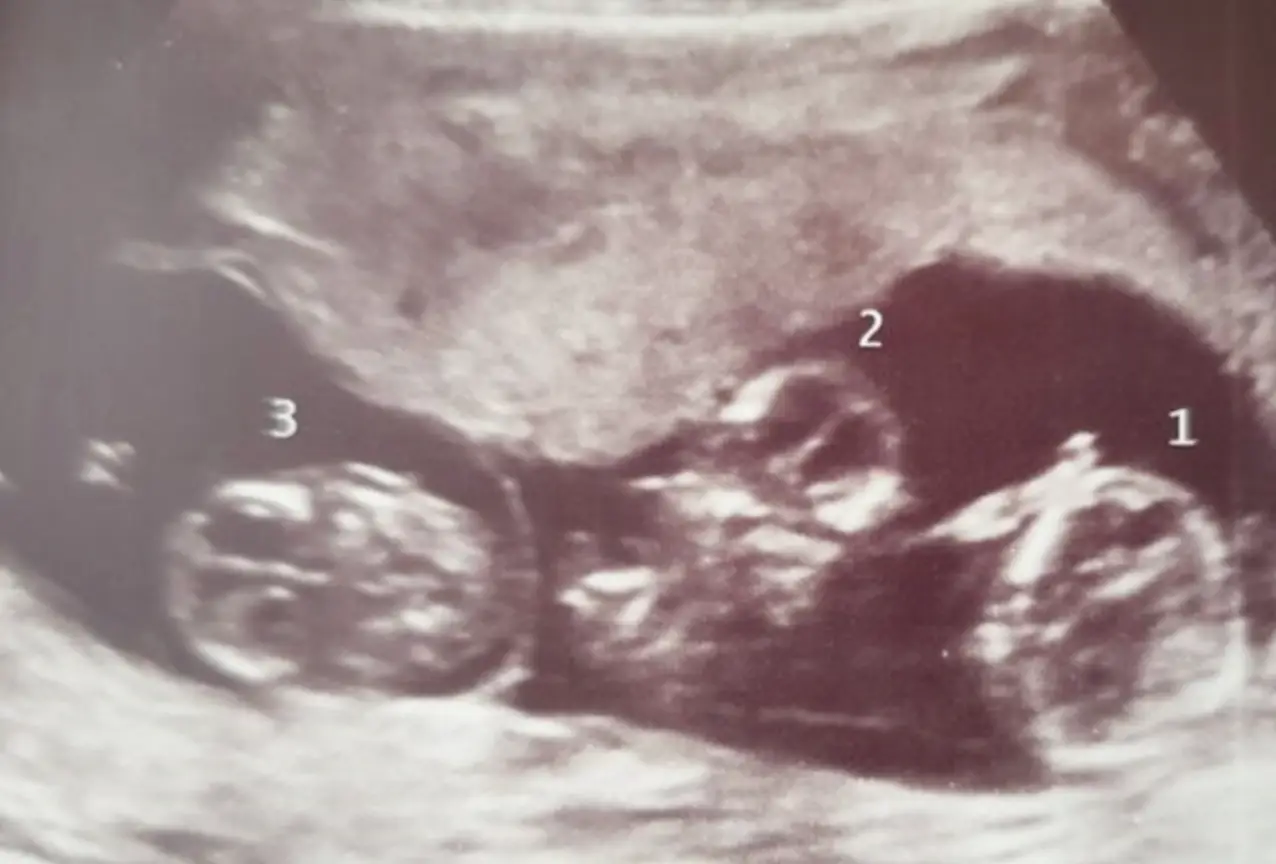

Her daughters Roya, Adina and Sefia back in December 2021. Zahra and her fiancé Ashraf Reid, 29, first discovered the triplets at her 12-week sᴄᴀɴ.

The triplets, known as spontaneous identical triplets, are now five months old and two of the babies, Roya and Adina, were sharing a placenta. Sefia, meanwhile, was on her own.

When they were born they looked so similar, so they got a test done and it showed they were all identical. The egg split once earlier in the pregnancy so she got her own placenta, then the second split happened a bit further along, but they are all from the same egg.